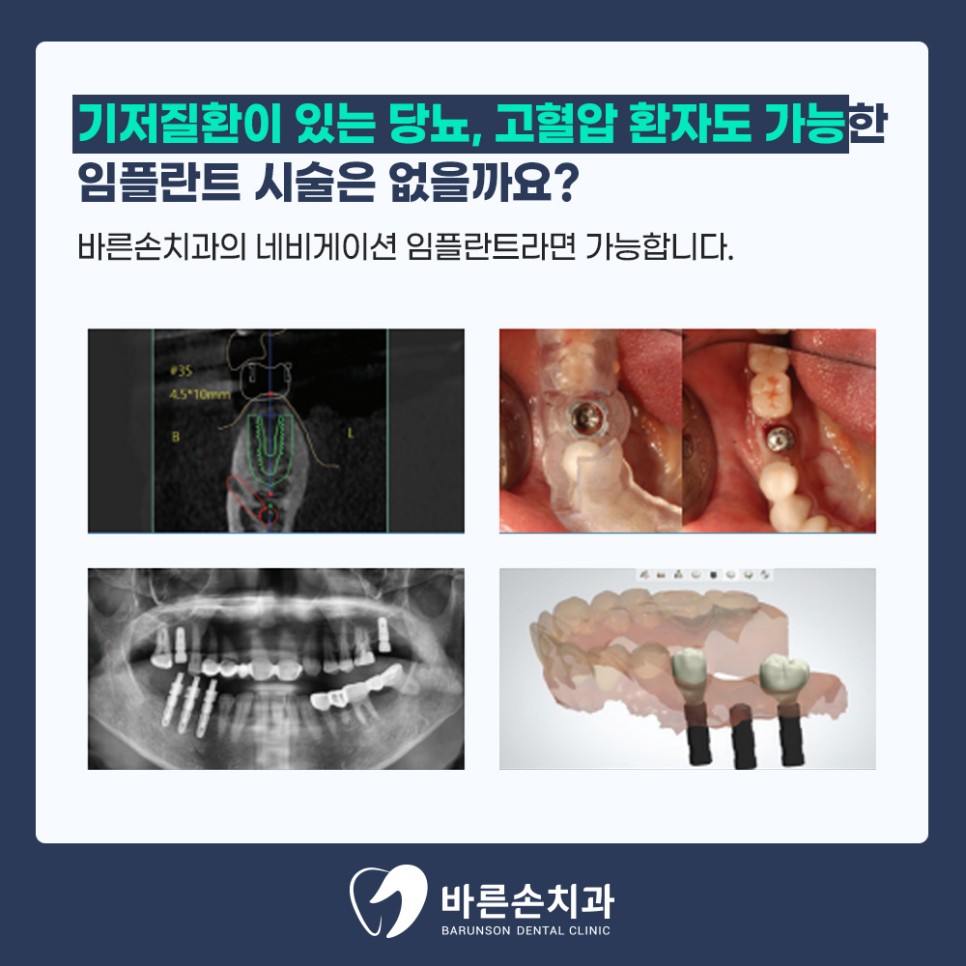

<네비게이션 임플란트란 무엇인가?!>

<네비게이션 임플란트란>

3D 컴퓨터 가상 수술과정을 통해 보이지 않는 뼛속 구조와 신경위치를 분석하여 임플란트의

개수, 식립위치, 방향, 각도 등을 미리 결정하고 가이드해주는 수술유도장치로

이를 통해 안전하고 정밀한 수술이 가능하도록 하는것 입니다.

다수의 임플란트를 쉽고 빠르게 식립할 수 있는게

<네비게이션 임플란트>의 장점인 만큼

치아가 상실되어 식사하시는데 지장이 있으신 분들은

언제든지 전화 및 내원 하시어 상담 받으시길 바랍니다^^